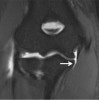

MRI : 팔꿈치 내측측부인대 파열(Ulnar collateral ligament tear)